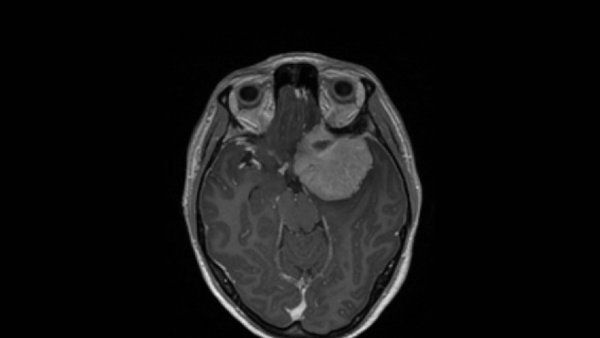

Toddler’s Brain Tumor Symptoms Subside Thanks to New Use of Epilepsy Laser Procedure